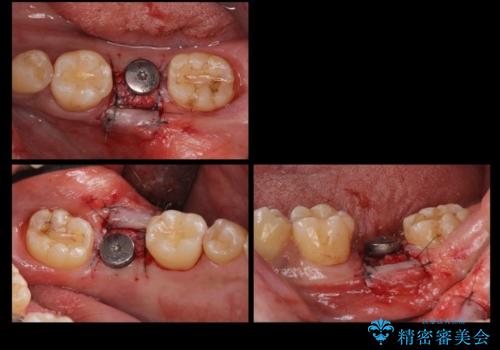

- 奥歯が割れたあと、他院で抜歯したところにインプラントを希望して来院。2回法で行いました。

奥歯を抜いたまま放置すると後方の歯が前に倒れこんでしまい、かみ合わせやその後の治療に支障がでます。早めに処置することをおすすめします。